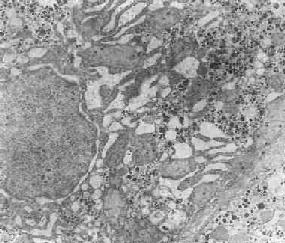

电子显微镜肿瘤病理检查